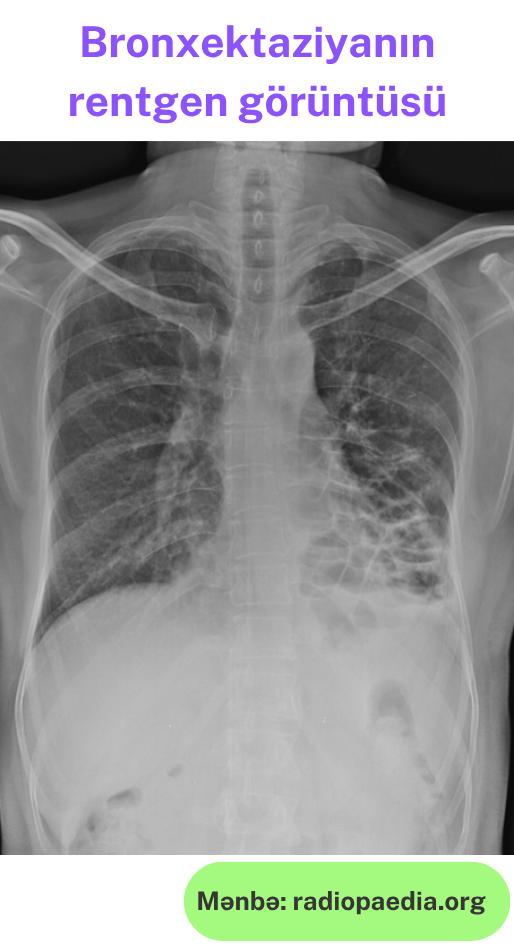

Rentgen müayinəsi və kompüter tomoqrafiya:

- Bronx divarlarının qalınlaşmasına görə "rels işarəsi" (paralel xətlər)

- Gecikmiş mərhələlərdə: "pətək ağciyər" görünüşü